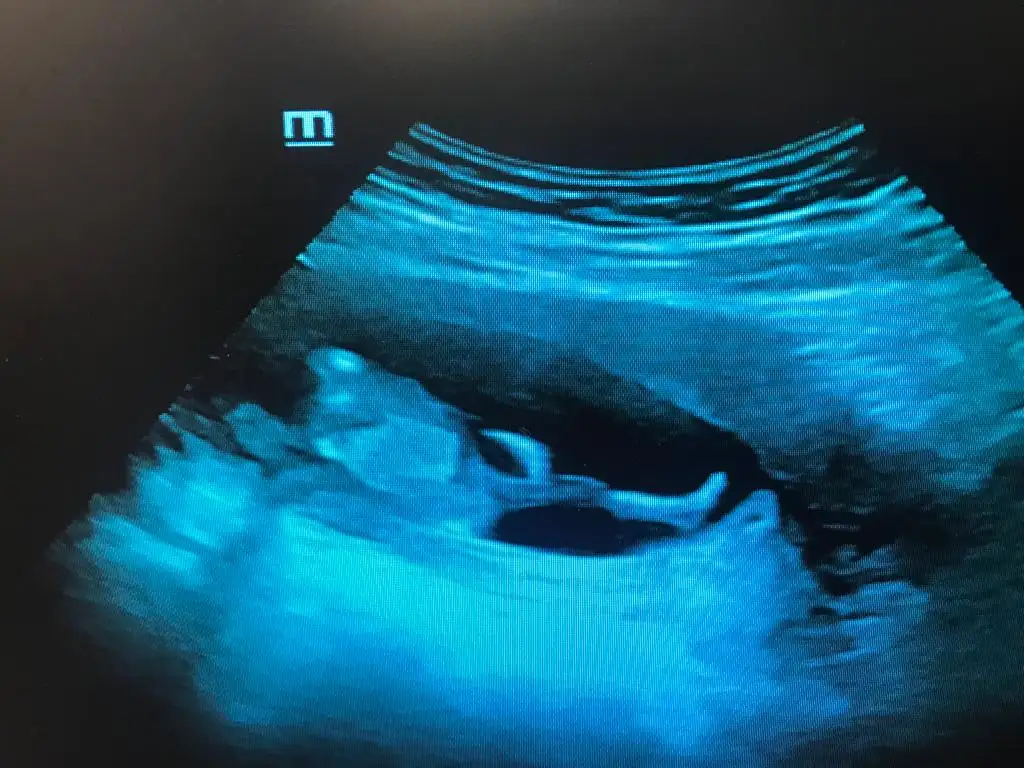

Bir de ultrason" deseniz.Neyse,utrasyon degil en azindan:)Selam Kızlarbir çok kişi gruplardan beni bilir. Yine yetiştim imdatlara

Çoook uzun bir süre araştırma okuma yaptıktan sonra sizlere bu başlığı açtım çevremde tüm gebelere de denedim. Bunun sırrını çözen İnstagramda (isim vermeyim) işi ticarete dökmüş bile.Nub, Ramzi,Çin Rus Japon Takvimleri, Yüzük Yöntemi bir çok şey size sayabilirim.

5 ve 14. haftaya kadar olan ultrasyon fotolarınızı paylaşın. Vajinadan mı yoksa karından mı çekildiğini ve kaç haftalık olduğunu da mutlaka belirtin.

Not: Tahmin yaptığım anneler cinsiyet öğrendikten sonra lütfen bana geri dönüş yapın![]()

Vajinal bakildi. 7. Haftadayim.karından mı? kaç haftalık?

canım kız gibi duruyor